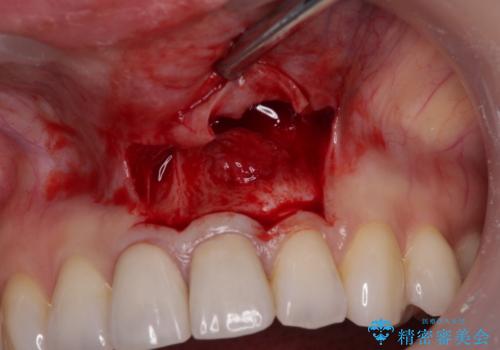

- 他院にて前歯2本をセラミッククラウンにしたものの、膿の出口ができて気になるとのことで来院された患者様です。

治療の選択肢としては、①セラミッククラウンを壊して再度根管治療を行い、その後セラミッククラウンを製作する、②当該歯の歯根端切除術を行う、のいずれかとなります。

歯根端切除術では、術後に歯肉ラインが偏位し、セラミッククラウンと歯の境目が目立つことがありますが、患者様と相談の上、②歯根端切除術にて治療を行うこととしました。